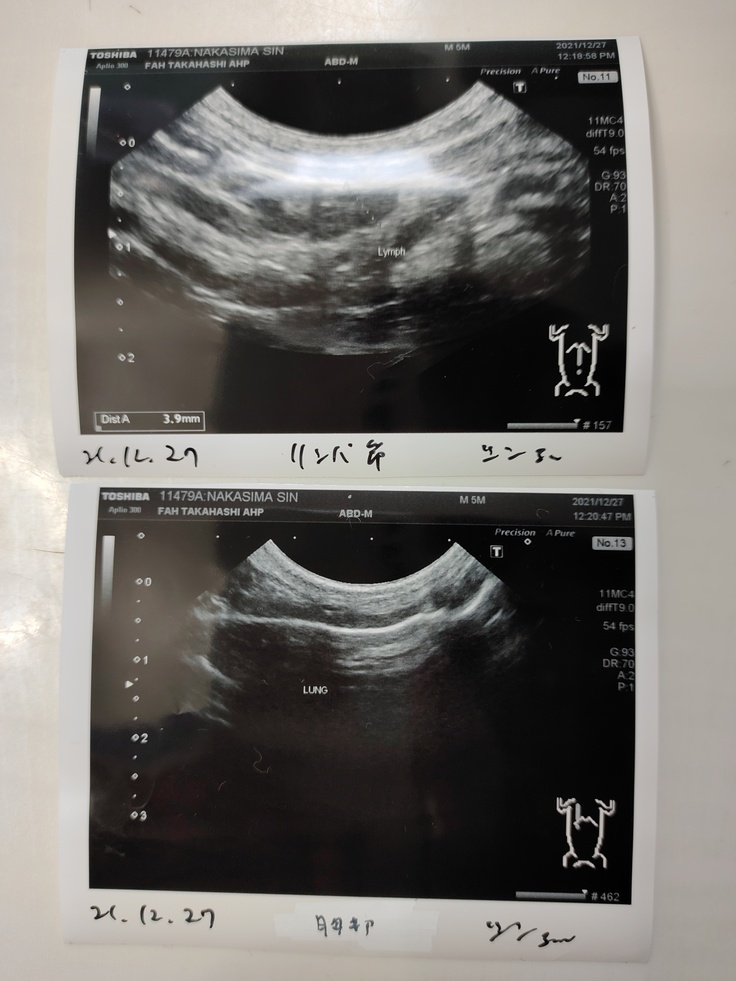

エコー写真

前回、3.2mmだったリンパが、少し大きくなっていて3.9mmになっていました。測り方の誤差の可能性もあるけど、"薬の量が足りてない可能性" もあるとの事でした。